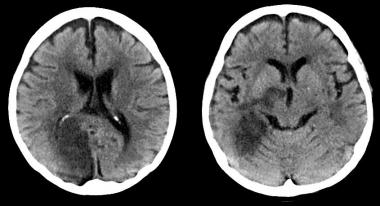

¿Cómo afecta la enfermedad carotídea extracraneal el tratamiento de la oclusión arterial intracraneal?

La obstrucción mayor del 50% de la carótida interna extracraneal no limitó el beneficio del tratamiento intraarterial agudo en el ictus isquémico de causa intracraneal. Annals of Internal Medicine, 23 de mayo de 2017